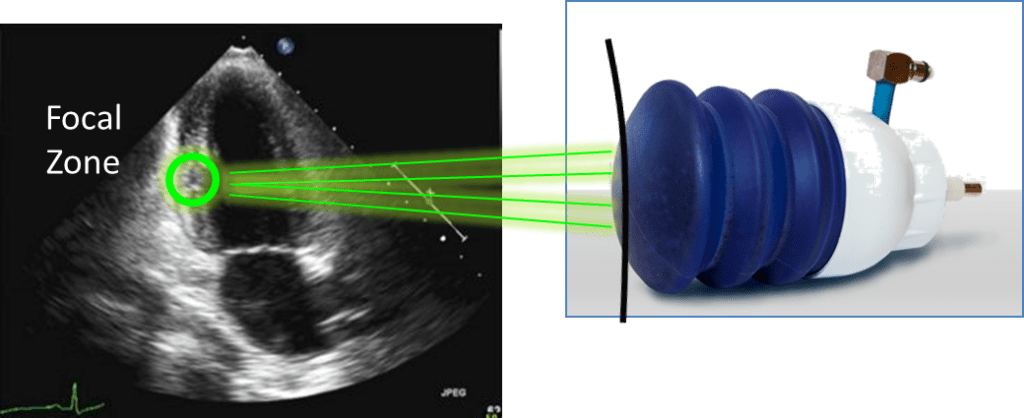

Shockwaves are special acoustics waves that can be targeted and focused non-invasively to a selected area inside the patient body.Shockwave therapy has been used in the last decades in Urology (kidney stone lithotripsy) and Orthopedics (plantar facilities) applications.A therapeutic effect is localized, precise (<2 mm precision) and control.

• Low-energy focused shock waves (energy density 0.09 mJ/mm2)

• Focused and controlled by echocardiography

• Released by ECG trigger (during the refractory phase of the cardiac cycle)